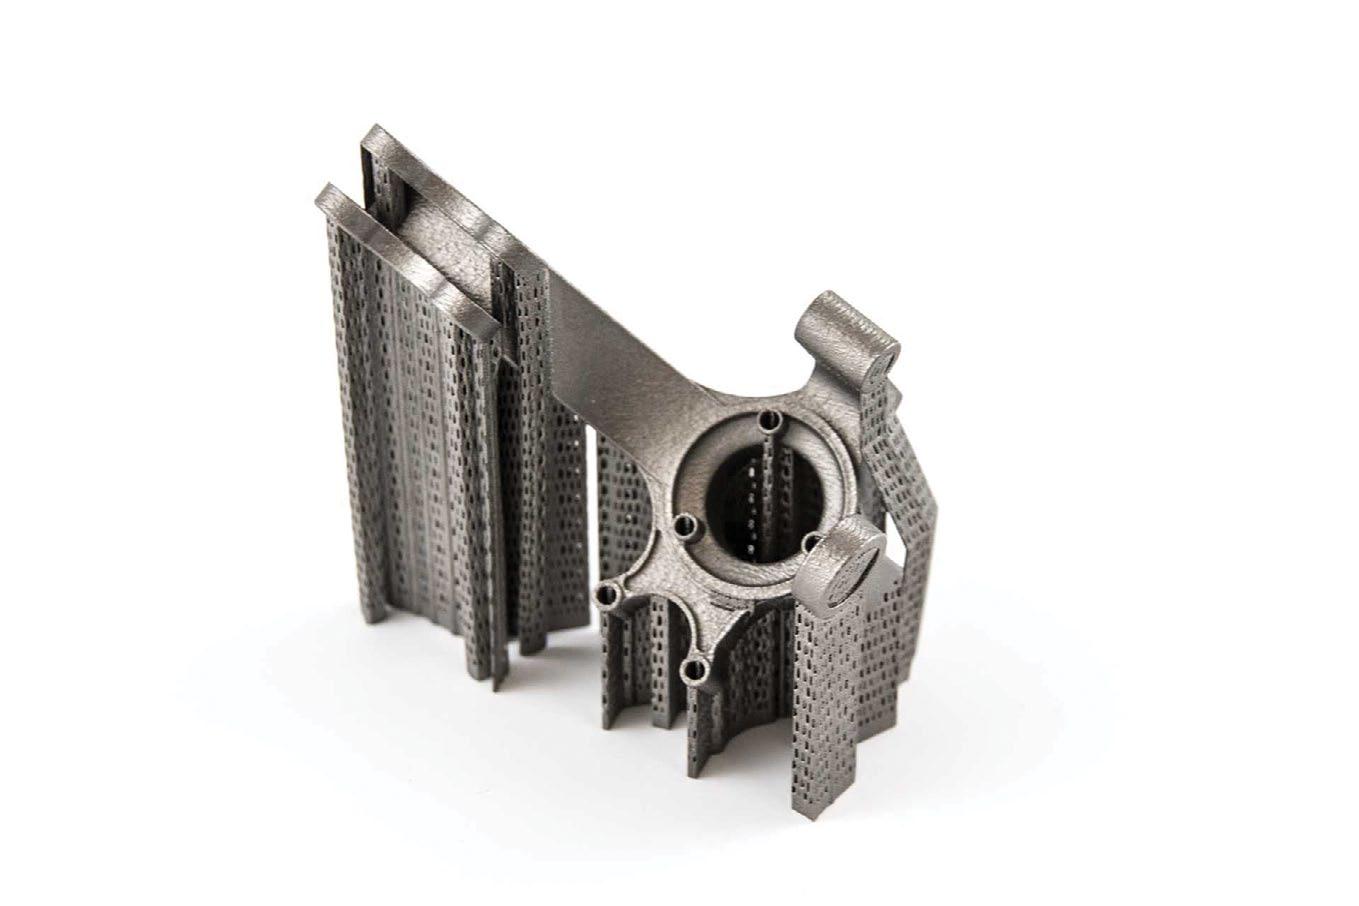

Recently, Materialise strengthened its unique position in the healthcare industry with its expanding implant (IP) portfolio of personalised solutions. A new patent has been accepted for Materialise’s 3D planning technologies and 3D-printed guides that enable the desired fixing of personalised implant products.

Materialise’s latest patent enables the design of screw replacements for the fit and fixation of customised implants. With the recent expansion of its portfolio of medical patents, the company continues to strengthen its unique position in the healthcare industry. At the same time, this supports its commitment to help patients worldwide through technological innovation.

With almost 30 years of experience in medical 3D printing and planning and an impressive IP portfolio of 160 medical patents granted, Materialise is in a unique position to support surgeons with advanced planning tools and personalised medical devices for complex patient cases.

This latest patent strengthens further the company’s 3D planning technologies and 3D printed guides that allow accurate planning and design of screw placements for customised implants, ensuring the desired fixation and optimal bone preservation.